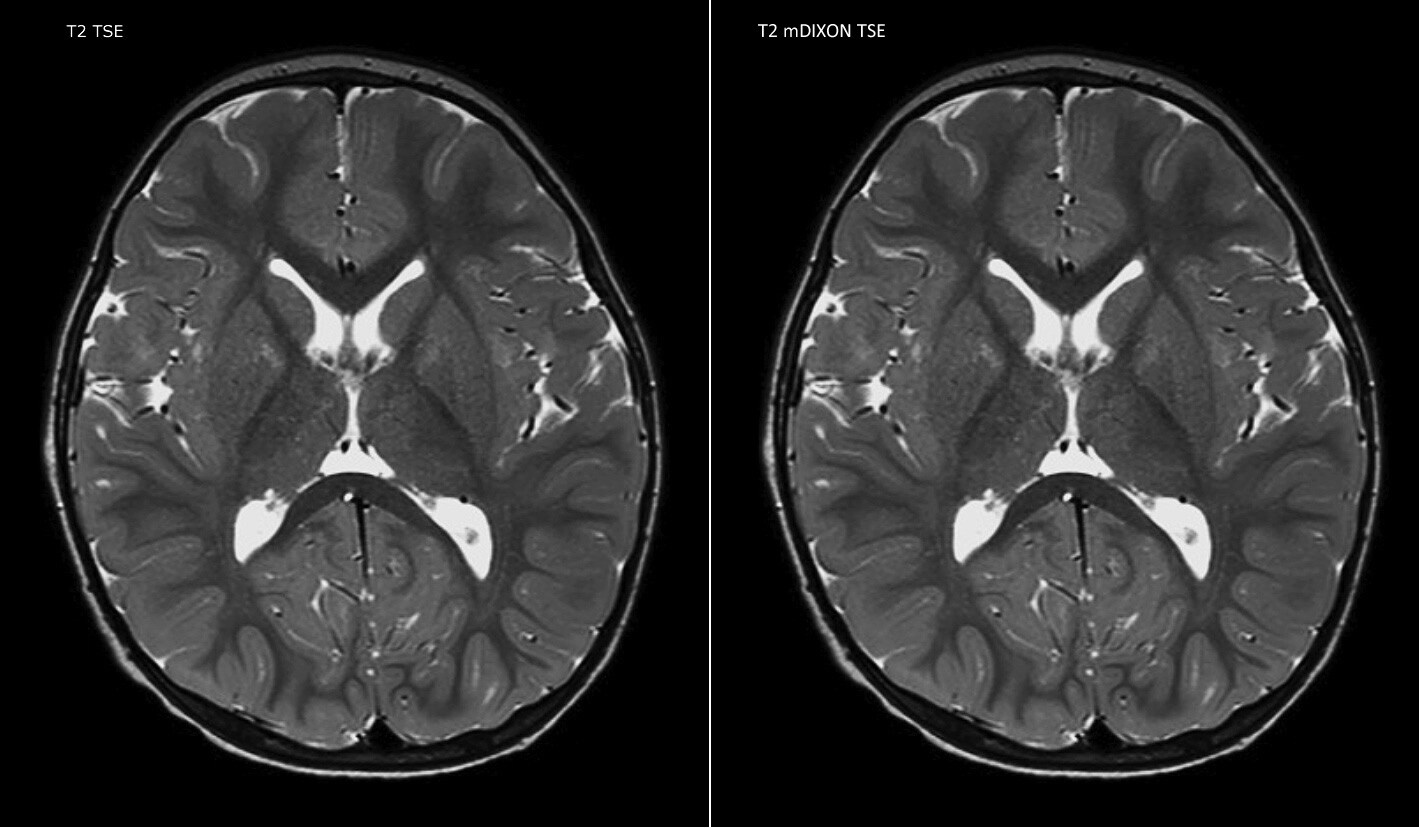

Philips mDIXON TSE ist ein Zweipunkt-DIXON-Verfahren, das Wasser- und Fettsignale trennt und so eine zeiteffiziente, fettfreie Bildgebung auch bei komplexen neurologischen Anatomien ermöglicht. „mDIXON TSE ist eine der signifikantesten Verbesserungen bei Bildgebungssequenzen, die wir am PCH bisher realisiert haben“, sagt Dr. Miller. „Dank der multiparametrischen Erfassung können wir Bilder mit Fettsuppression und entsprechende T2-Bilder ohne Fettsuppression in derselben Sequenz aufnehmen. Außerdem war es bei den bisherigen Methoden möglich, dass diese durch Artefakte aufgrund einer ungünstigen Patientenanatomie oder durch Bedienfehler beeinträchtigt wurden. Mit mDIXON verfügen wir jetzt jedoch über eine robuste und zuverlässige Methode zur Fettsuppression.“ Historisch gesehen bereitet die Fettsuppression am Ende des Sichtfeldes Schwierigkeiten, insbesondere bei der Bildgebung der gesamten Wirbelsäule und bei diffizilen Patientenanatomien wie dem unteren Halsbereich. „Aufgrund der einzigartigen Fettsuppressionseigenschaften von mDIXON treffen diese Probleme jedoch nicht mehr zu“, erläutert Dr. Miller. „Wir erhalten routinemäßig eine homogene Fettsuppression unter praktisch allen Bedingungen. Darüber hinaus konnten wir auch die Effizienz steigern, weil wir keine Sequenzen mehr aufgrund solcher technischen Einschränkungen wiederholen müssen.“

„mDIXON TSE hat unsere Diagnosesicherheit erhöht, weil Abweichungen, bei denen die Fettsuppression für die Diagnose entscheidend ist, definitiv abgeklärt werden können, zum Beispiel metastatische Erkrankungen oder ossale Veränderungen.“

„mDIXON TSE erweist sich bei Patienten mit Läsionen oder pathologischen Befunden im Weichteilgewebe wie Gesicht und Hals am nützlichsten sowie bei Patienten mit kontrastverstärkenden Abweichungen, die mit Fettsuppression am besten sichtbar sind“, so Dr. Miller weiter. „Unsere gesamte Wirbelsäulenbildgebung enthält mittlerweile mDIXON T2-Bilder auf reiner Wasserbasis, und dies ermöglicht uns die Erkennung von Pathologien, die bei einer Bildgebung ohne Fettsuppression zum Beispiel von Knochenverletzungen nicht sichtbar wären. Außerdem ist es nicht nötig, weitere TSE-T2-Standardbilder aufzunehmen, weil die mDIXON In-Phase-Bilder gleichwertig mit TSE-T2-Standardbildern sind.“